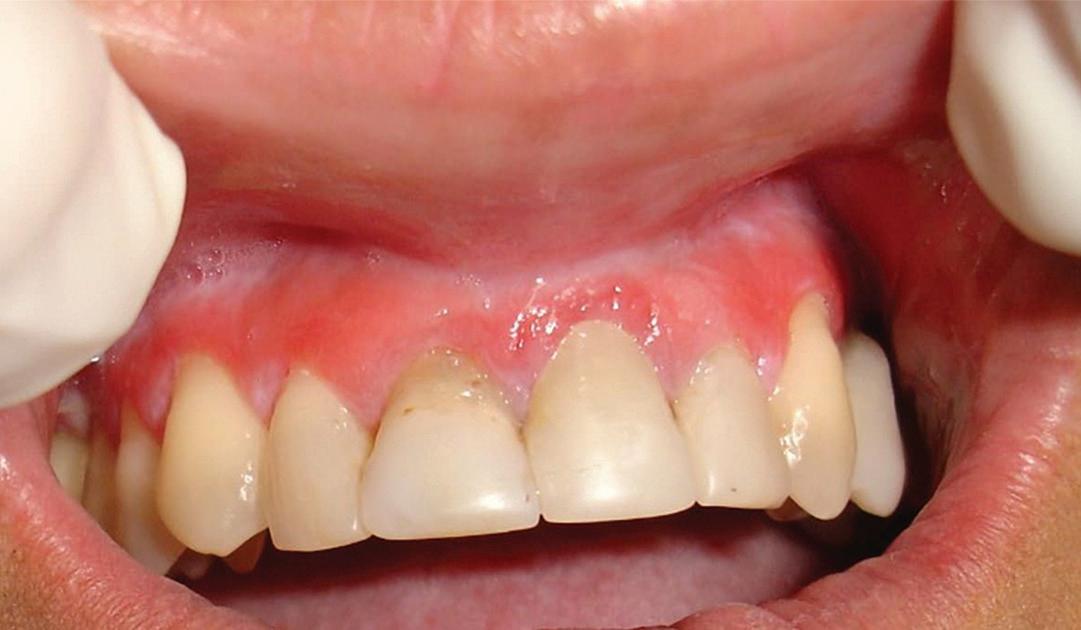

Tooth replacement from extraction to restoration. 3. Second-stage and impression procedures

The third part of this series reviews uncovering of implants that were buried in a 2-stage approach, provisionalization of the implant, and impression and scanning techniques.1 These techniques are all crucial for the final restorative outcome of the implant. The uncovering and second-stage procedures set the foundation for the shape and position of the soft tissue, which are very important esthetic factors. This information must also be properly transferred to the laboratory via a highly accurate impression so the laboratory has as much information as possible. If these steps are done properly, the result will be implant crowns that are easy to seat, biologically ideal, and esthetically pleasing.